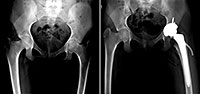

Анастасии 12 лет, она из города Киржач Владимирской области. Диагноз – двусторонний коксартроз 3 степени слева, 2 степени справа. В ФБГУ «Российская детская клиническая больница» ей планируют установить эндопротез левого тазобедренного сустава Aesculap (Германия). Оплата эндопротеза за счет бюджетных средств не производится. Стоимость базовой комплектации эндопротеза с гранулами «ReproBone» для регенерации костной ткани составляет 218 540 рублей.

Мы с мужем поехали в Детскую Областную Центральную больницу г. Владимир на приём к травматологу – ортопеду со всеми снимками и анализами и выпросили направление в Москву в Российскую детскую клиническую больницу. Записались на приём к врачу травматологу – ортопеду Кузину А.С. Врач посмотрел снимки и поставил диагноз: остеоид – остеома средней трети левой бедренной кости, двусторонний коксартроз.